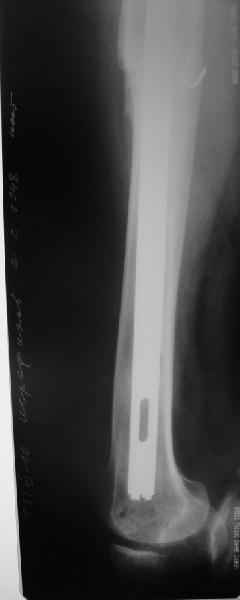

Уважаемые коллеги, в данном случае в лечении стандартного перипротезного перелома В2 Ванкуверской классификации (перелом вокруг ножки эндопртеза с потерей стабильности ножки при хорошем - не требующем пластики - качестве кости.Parvizi J, Rapuri VR, Purtill JJ, et al (2004) Treatment protocol for proximal femoral periprosthetic fractures. J Bone Joint Surg Am; 86-A Suppl 2:8-16)с успехом применён оригинальный, но малоизведанный способ лечения подобных повреждений. В результате и последующие рекомендации не могут быть стандартными. В подобных случаях, как это уже дискутировалось год назад, можно было выполнить ревизию длинной ножкой, во многом работающей как интрамедуллярный гводь + плюс кабель/серкляж в проксимальном отделе. Или, оставить имеющуюся ногу плюс длинная пластиа с кабелем/серкляжем, можно разными современными блокированными *примочками*. В таком случае при достижении консолидации пластина удаляется, тк при возникновении в будущем потребности в ревизии имеющийся дополнительный металл и без затруднит непростое вмешательство (кто пробовал, знает о чём я говорю). С длинной ногой, конечно, так же всё понятно. В данном случае мы имеем некую комбинацию, осложнённую отсутствием репозиции и фиксации в прошлом отломков вокруг ножки. Поэтому не каждый в данном случае рискнёт утверждать за счёт какого из компонентов системы - дистального либо проксимального обеспечивается стабильность. А если это и фиксация и за счёт ножки и за счёт гвоздя - каков баланс между данными компонентами в поддержании стабильности ситемы. То есть, я надеюсь, что дистального смещения ножки здесь не будет при условии сохранения как гвоздя, так и блокирующих винтов. При удалении же гвоздя возможна миграция ножки, только винтов - всей системы. Здесь же перелом (надеюсь, его не будет) блокирующих винтов может быть первым свидетельством механического неблагополучия системы... А так, помимо отличного результата этот случай так же косвенно подтверждает известную истину - Эндопротез, к сожалению, требует периодической замены. И выполняя фиксацию перипротезного перелома, а в последующем решая вопрос об удалении имплантатов, мы вынуждены думать и о функции сустава, и о том, как в будущем выполнить ревизию. Если ожидаемая продолжительность жизни пациента заставляет нас об этом думать. С уважением, Андрей

Это сплошной титановый стержень. На дистальном конце отверстия под кондуктор. На другом - канал под ножку глубиной 60 мм, стенки толщиной 2,5-3 мм. И там же продольный пропил, чтобы канал мог адаптироваться к ножке.

Дорогой Александр Николаевич! Спасибо, что держите всех нас в курсе.

Сейчас опорную нагрузку на бедро берет на себя система от бедренного компонента эндопротеза до проксимального винта в интрамедуллярном гвозде. Свидетельство тому - реакция кортикала утолщением вокруг того самого винта. Таким образом вся кость от верхушки б.вертела до проксимального винта не испытывает физиологической осевой нагрузки. Результатом этого могут стать следующие последствия друг друга не исключающие: 1) все будет хорошо до перелома опорной системы по винту(ам) или в месте соединения штифта с ножкой или еще где-либо, 2) исключенная из-под нагрузки кость будет терять в количестве и качестве, что не очень (или очень не) хорошо для возможных будущих ревизий (тьфу-тьфу!!!).